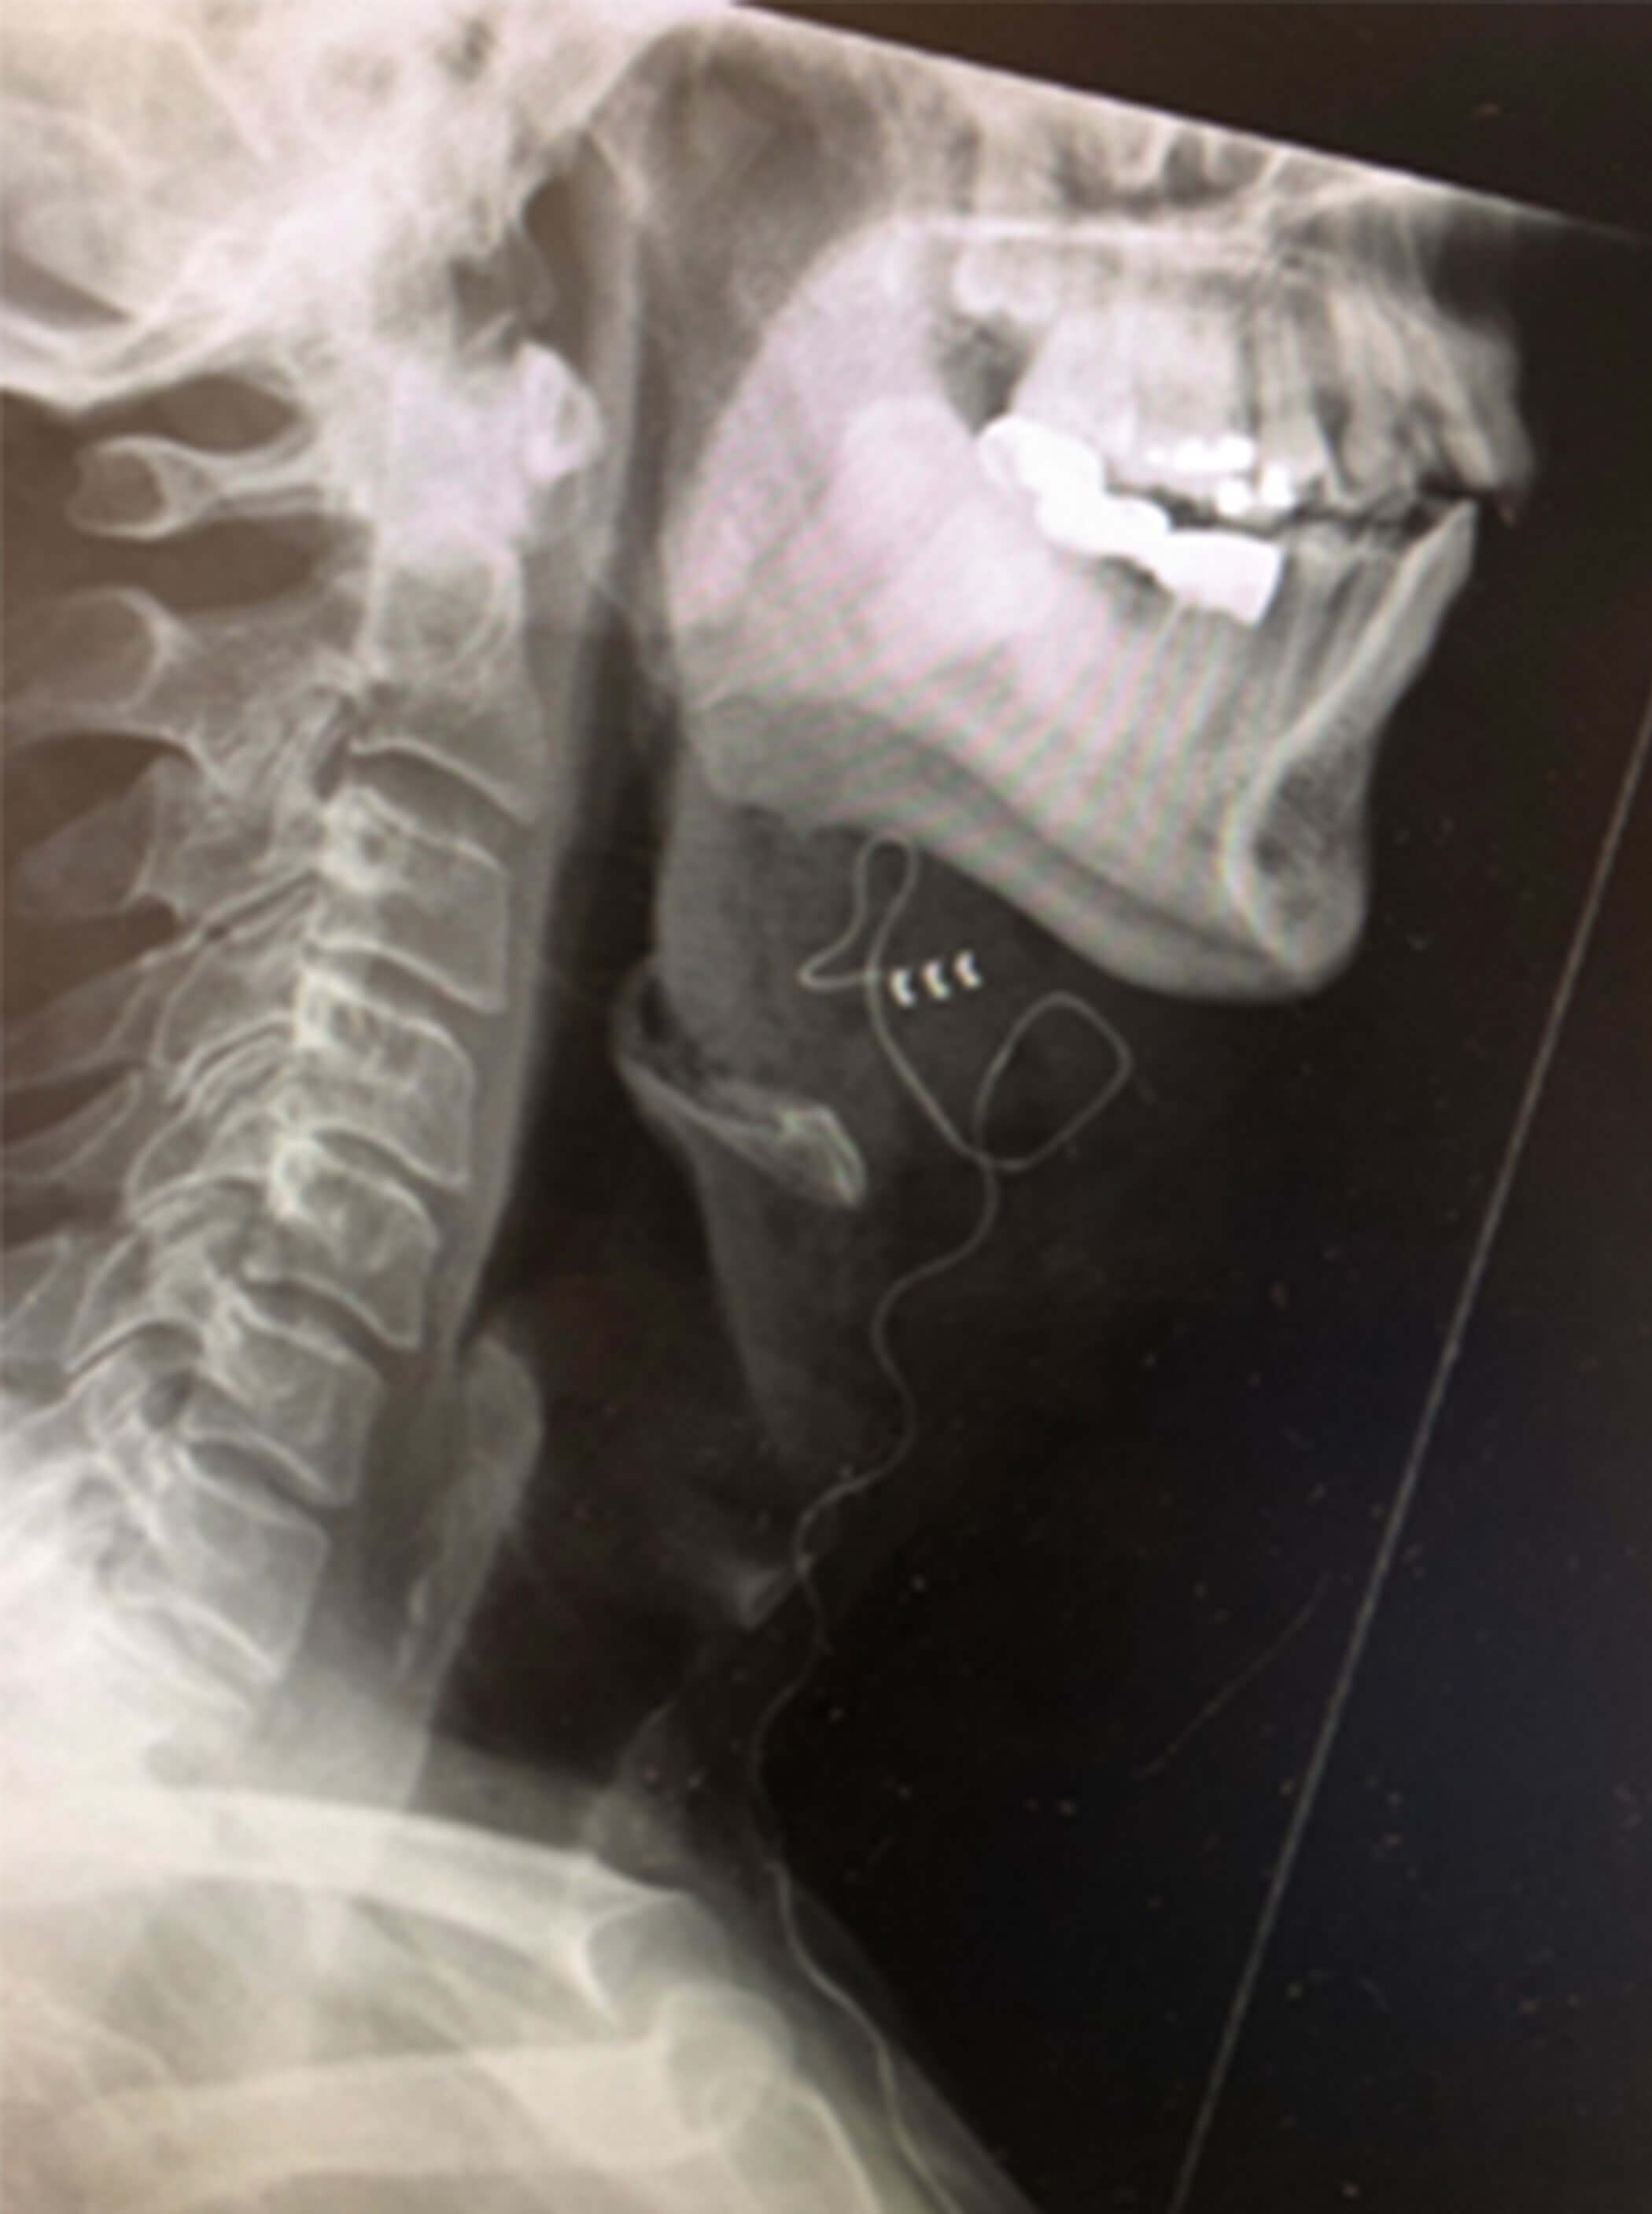

Figure 2d. Postoperative right lateral neck X-Ray showing the electrode cuff

placed on the anterior branches of the hypoglossal nerve.